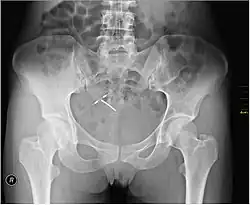

An intrauterine device (IUD), also known as intrauterine contraceptive device (IUCD or ICD) or coil, is a small, often T-shaped birth control device that is inserted into the uterus to prevent pregnancy.